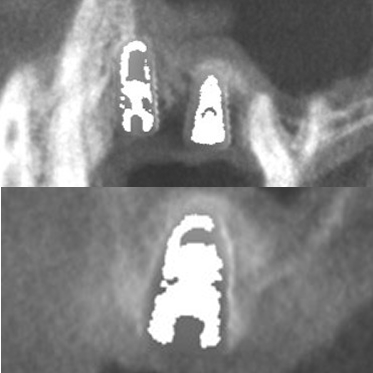

● 上の顎の奥歯にインプラントを入れるのに骨が足りないため、ソケットリフトと人工骨補填して骨造成を行った症例1

術前

藤沢デンタルオフィスのインプラント術前 藤沢デンタルオフィスのインプラント術前

3Dシミュレーション

術後

藤沢デンタルオフィスのインプラント術後 藤沢デンタルオフィスのインプラント術後

シミュレーション通りの上顎洞底挙上と人工骨補填(3Dガイドシステム使用)